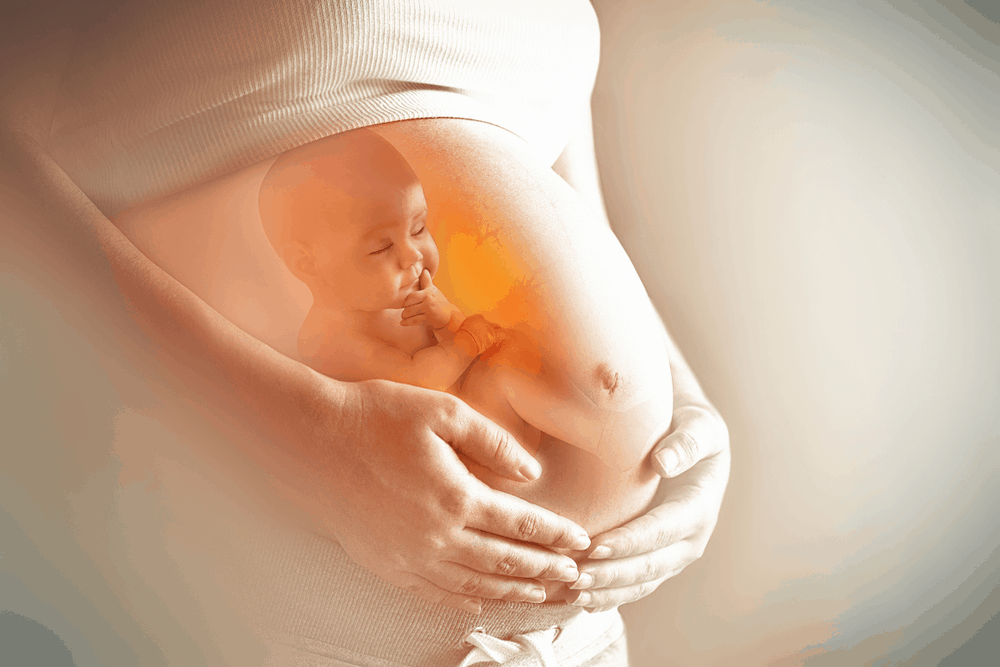

ကိုယ်ဝန်ဆောင်မေမေ သန်ချလို့ရလား

ကိုယ်ဝန်ဆောင်ချိန်မှာ မေမေရော ဗိုက်ထဲက ဘေဘီလေးပါ ကျန်းမာစေဖို့အတွက် အနေအထိုင် အစားအသောက် အစစအရာရာကို ဂရုစိုက် ရပါတယ်။ အစားအသောက်ကိုတောင် ဂရုစိုက်နေရချိန်မှာ ဆေးသောက်ဖို့ဆိုရင် ပိုပြီးတောင် ဂရုစိုက်ရမှာပါ။ ဒီလို အစစအရာရာ ဂရုစိုက်နေရချိန်မှာ သိချင်နေလောက်မယ့် မေးခွန်းလေးတစ်ခု အကြောင်း ပြောပြပေးချင်ပါတယ်။ ဒါကတော့ ကိုယ်ဝန်ဆောင်မေမေ သန်ချလို့ရလား ဆိုတာပါ။ ကိုယ်ဝန်ဆောင်ချိန်မှာ သန်ချလို့ရလား ဆိုတာကို မပြောခင် သန်ချတာနဲ့ ပတ်သက်တဲ့ အကြောင်းလေး ပြောပြပေးချင်ပါတယ်။ ဘာတွေကများ ကိုယ်ဝန်ဆောင် မေမေတွေကို သန်ထစေတာလဲ ကိုယ်ဝန်ဆောင် မေမေတွေကို သန်ထစေတဲ့ အကြောင်းအရင်းတွေကတော့ သေချာ ကျက်အောင် မချက်ထားတဲ့ ငါးတွေကို စားတာ သေချာ ကျက်အောင် ချက်မထားတဲ့ ဝက်သားစားတာ သေချာ ချက်မထားတဲ့ အမဲသား စားမိတာ လူတွေဆီကနေ အချင်းချင်း ကူးစက်ခံရတာ […]